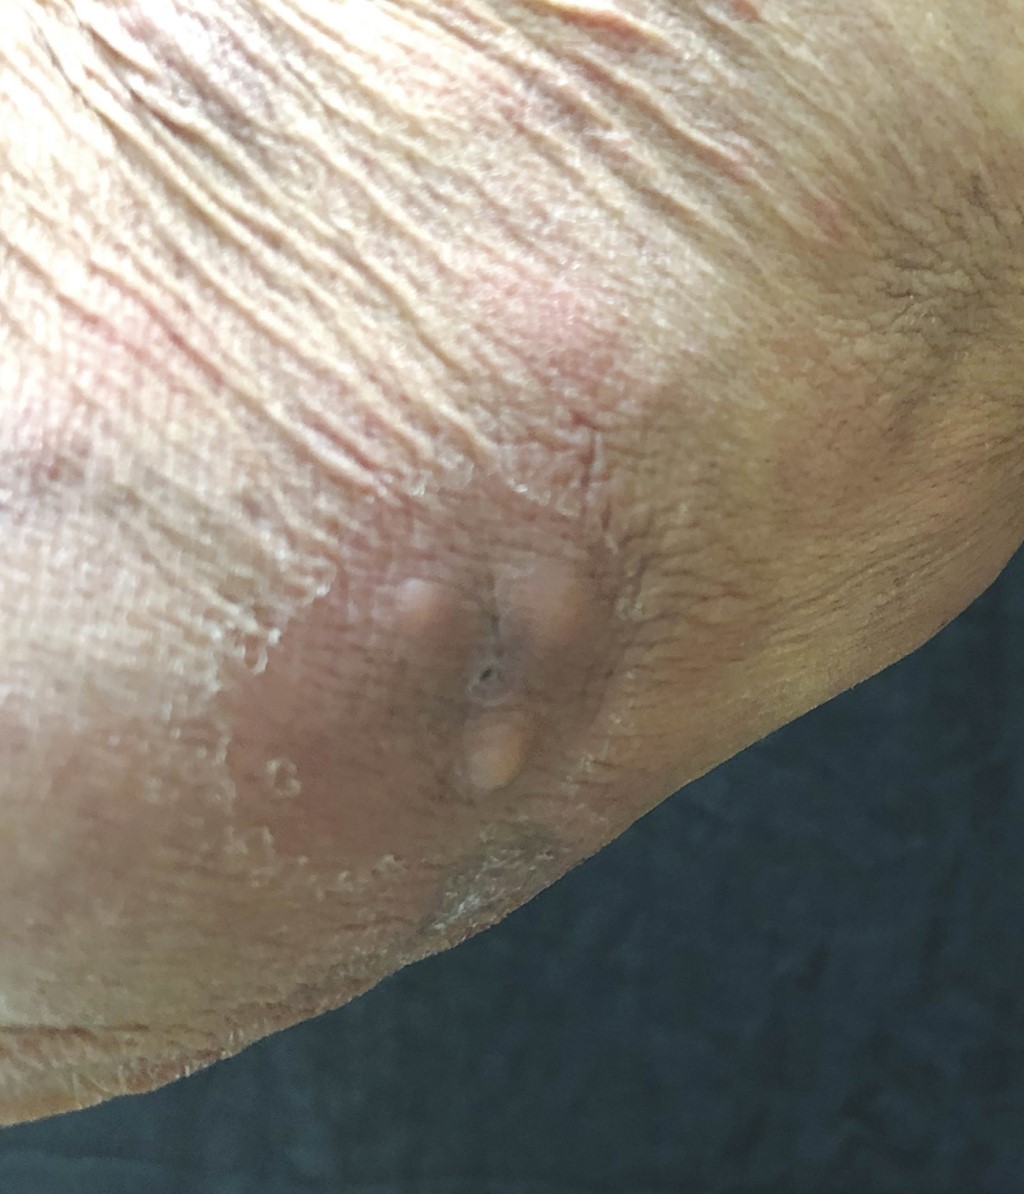

Paciente del sexo masculino, de 78 años de edad, originario y residente de San Juan de los Ríos, Puebla, de ocupación campesino, sin antecedentes de importancia para padecimiento actual, quien acude al Centro Dermatológico "Dr. Ladislao de la Pascua" refiriendo la presencia de "granos" en extremidades y en tronco, con una evolución de un año y medio. Como síntomas refería prurito ocasional. Tratado previamente con múltiples antibióticos: cefixima, minociclina, trimetoprima-sulfametoxazol, además de loratadina y dexametasona, sin mejoría. A la exploración física se observa dermatosis diseminada a cabeza, tronco, extremidades superiores e inferiores. De la primera, afecta cara en región frontal y lóbulos de orejas; de la segunda, principalmente tórax anterior y posterior a nivel de tercios superior y medio así como región lumbar; de la tercera, compromete brazos y antebrazos por todas sus caras, y de la última, muslos. Bilateral y con tendencia a la simetría. Dermatosis de aspecto monomorfo, polilesional, constituida por eritema, manchas hiperpigmentadas color marrón oscuro, así como algunas lesiones de aspecto nodular, elementos que confluían para formar placas de bordes mal limitados, de diferente forma y tamaño, cubiertas con fina escama blanquecina. De evolución crónica (Figuras 1, 2 y 3). El paciente refería disestesias difusas en miembros torácicos y pélvicos. Resto de interrogatorio negativo.

Figura 2

Figura 3